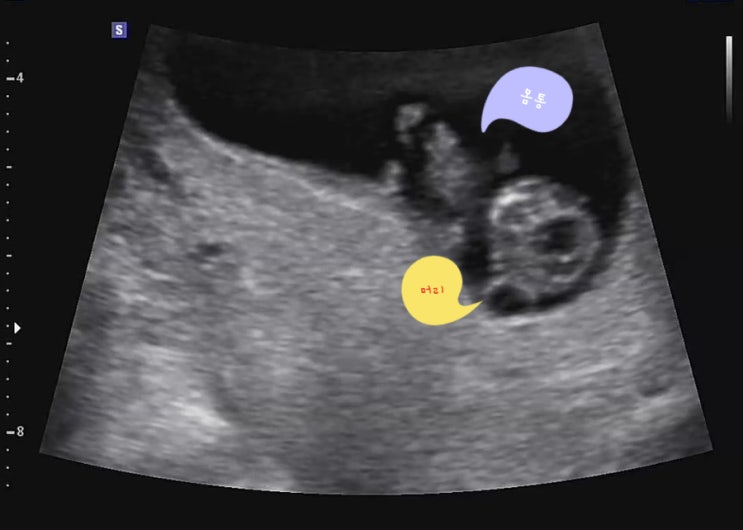

[임신일기]15 신생아빨래 32주차초음파 임신31주차~임신32주차

레인부츠 크기가 된 31주차~ 두 달도 안남았다고 생각하니 이제 슬~슬~ 아기 맞이 준비를 해야한다 아가를 ...